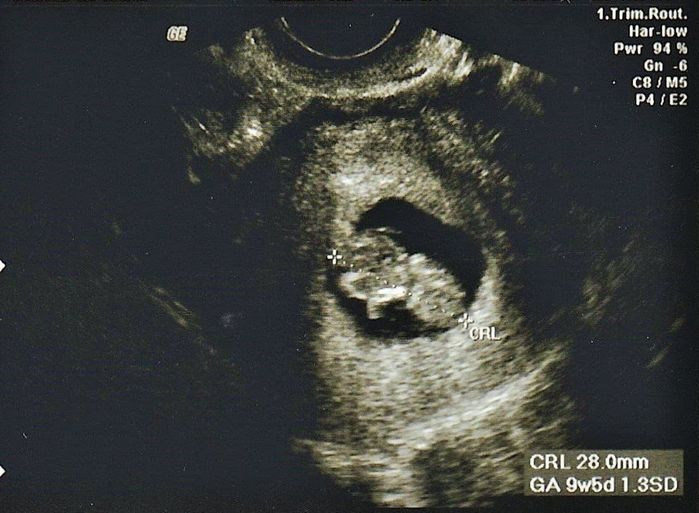

妊娠9週目のエコー写真

4D画像で頭、手、足を見ることができました。枝豆のような頭の形でなんだかかわいい、と早くも親バカ。この時期は、子宮がんや感染症の免疫の有無など、様々な検査を行いました。実母に、私がはしかやおたふく風邪にかかったかなどや、母がどのような妊娠・出産をしたかを教えてもらいました。